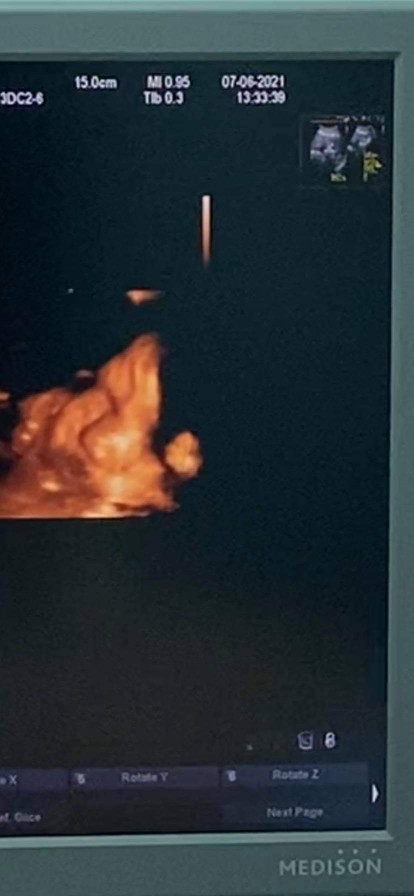

อันนี้ที่ไปซาวด์ล่าสุดอาทิตย์ที่แล้ว ตอนนี้29w6dแล้วค่ะ ทีมสิงหา ซาวด์4มิติบ่อยมากกกกก ทุกเดือนเลยก็ว่าได้ เห่อๆหน่อยค่ะแม่😂

ตอนซาวด์33+5weeks เอามือบัง แต่ก็ยังดีที่ให้แม่เห็น กรกฎาคมเหมือนกันคะ อยากเจอหน้าแล้ว🥰

บ้านนี้ตอน36week 4dayจ้ากำหนดคลอด 1ก.ค อยากแตกแย่แล้ว ตอนนี้อายุครรภ์38week3dayจ้าา

บ้านนี้กำหนดคลอด 6 กค. 64 ลูกสาวค่ะ ซาวด์ 4 มิติตอน24 สัปดาห์ ค่ะ

หมอลลิตาเหมือนกันค่ะ แต่น้องให้เห็นแค่นี้ ซาวด์ตอน 32w

30w ค่ะ ไม่เคยเห็นเต็มหน้าสักที ต้องเอามือมาบังตลอด

น้องไม่หันหน้าให้ดูเต็มๆเลยค่ะหันข้างให้ตลอด🥰